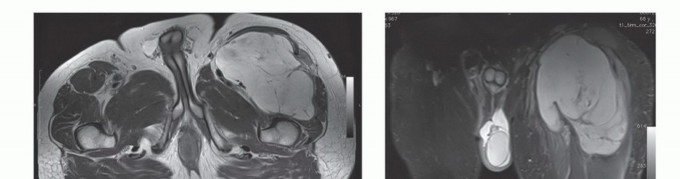

تُعد الأشعة المقطعية (CT) والتصوير بالرنين المغناطيسي (MRI) ضرورية لتحديد موقع ومدى الورم وعلاقته بعظم الفخذ والحزمة العصبية الوعائية.

التصوير بالرنين المغناطيسي (MRI): يُعتبر التصوير بالرنين المغناطيسي الأداة الأكثر قيمة لتقييم أورام الأنسجة الرخوة. يوفر صورًا مفصلة للأنسجة الرخوة، مما يساعد في تحديد حجم الورم وشكله وعلاقته بالعضلات والأوعية الدموية والأعصاب المحيطة. يمكن أن يوضح ما إذا كان الورم قد اخترق اللفافة أو امتد إلى حجرات أخرى. الأورام الكبيرة في العضلة الرباعية غالبًا ما تُزيح الأوعية الفخذية السطحية والعميقة. من المهم تحديد العلاقات التشريحية لهذه الأوعية بالورم قبل الاستئصال.